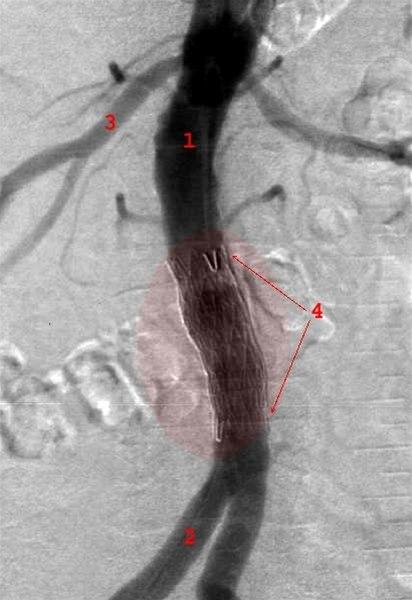

Aorta stentgraft

Aneurisme i bukaorta

Behandlet med stentgraft innlagt via lysken

- Aorta

- A. iliaca communis

- Nyrearterie

- Stentgraft